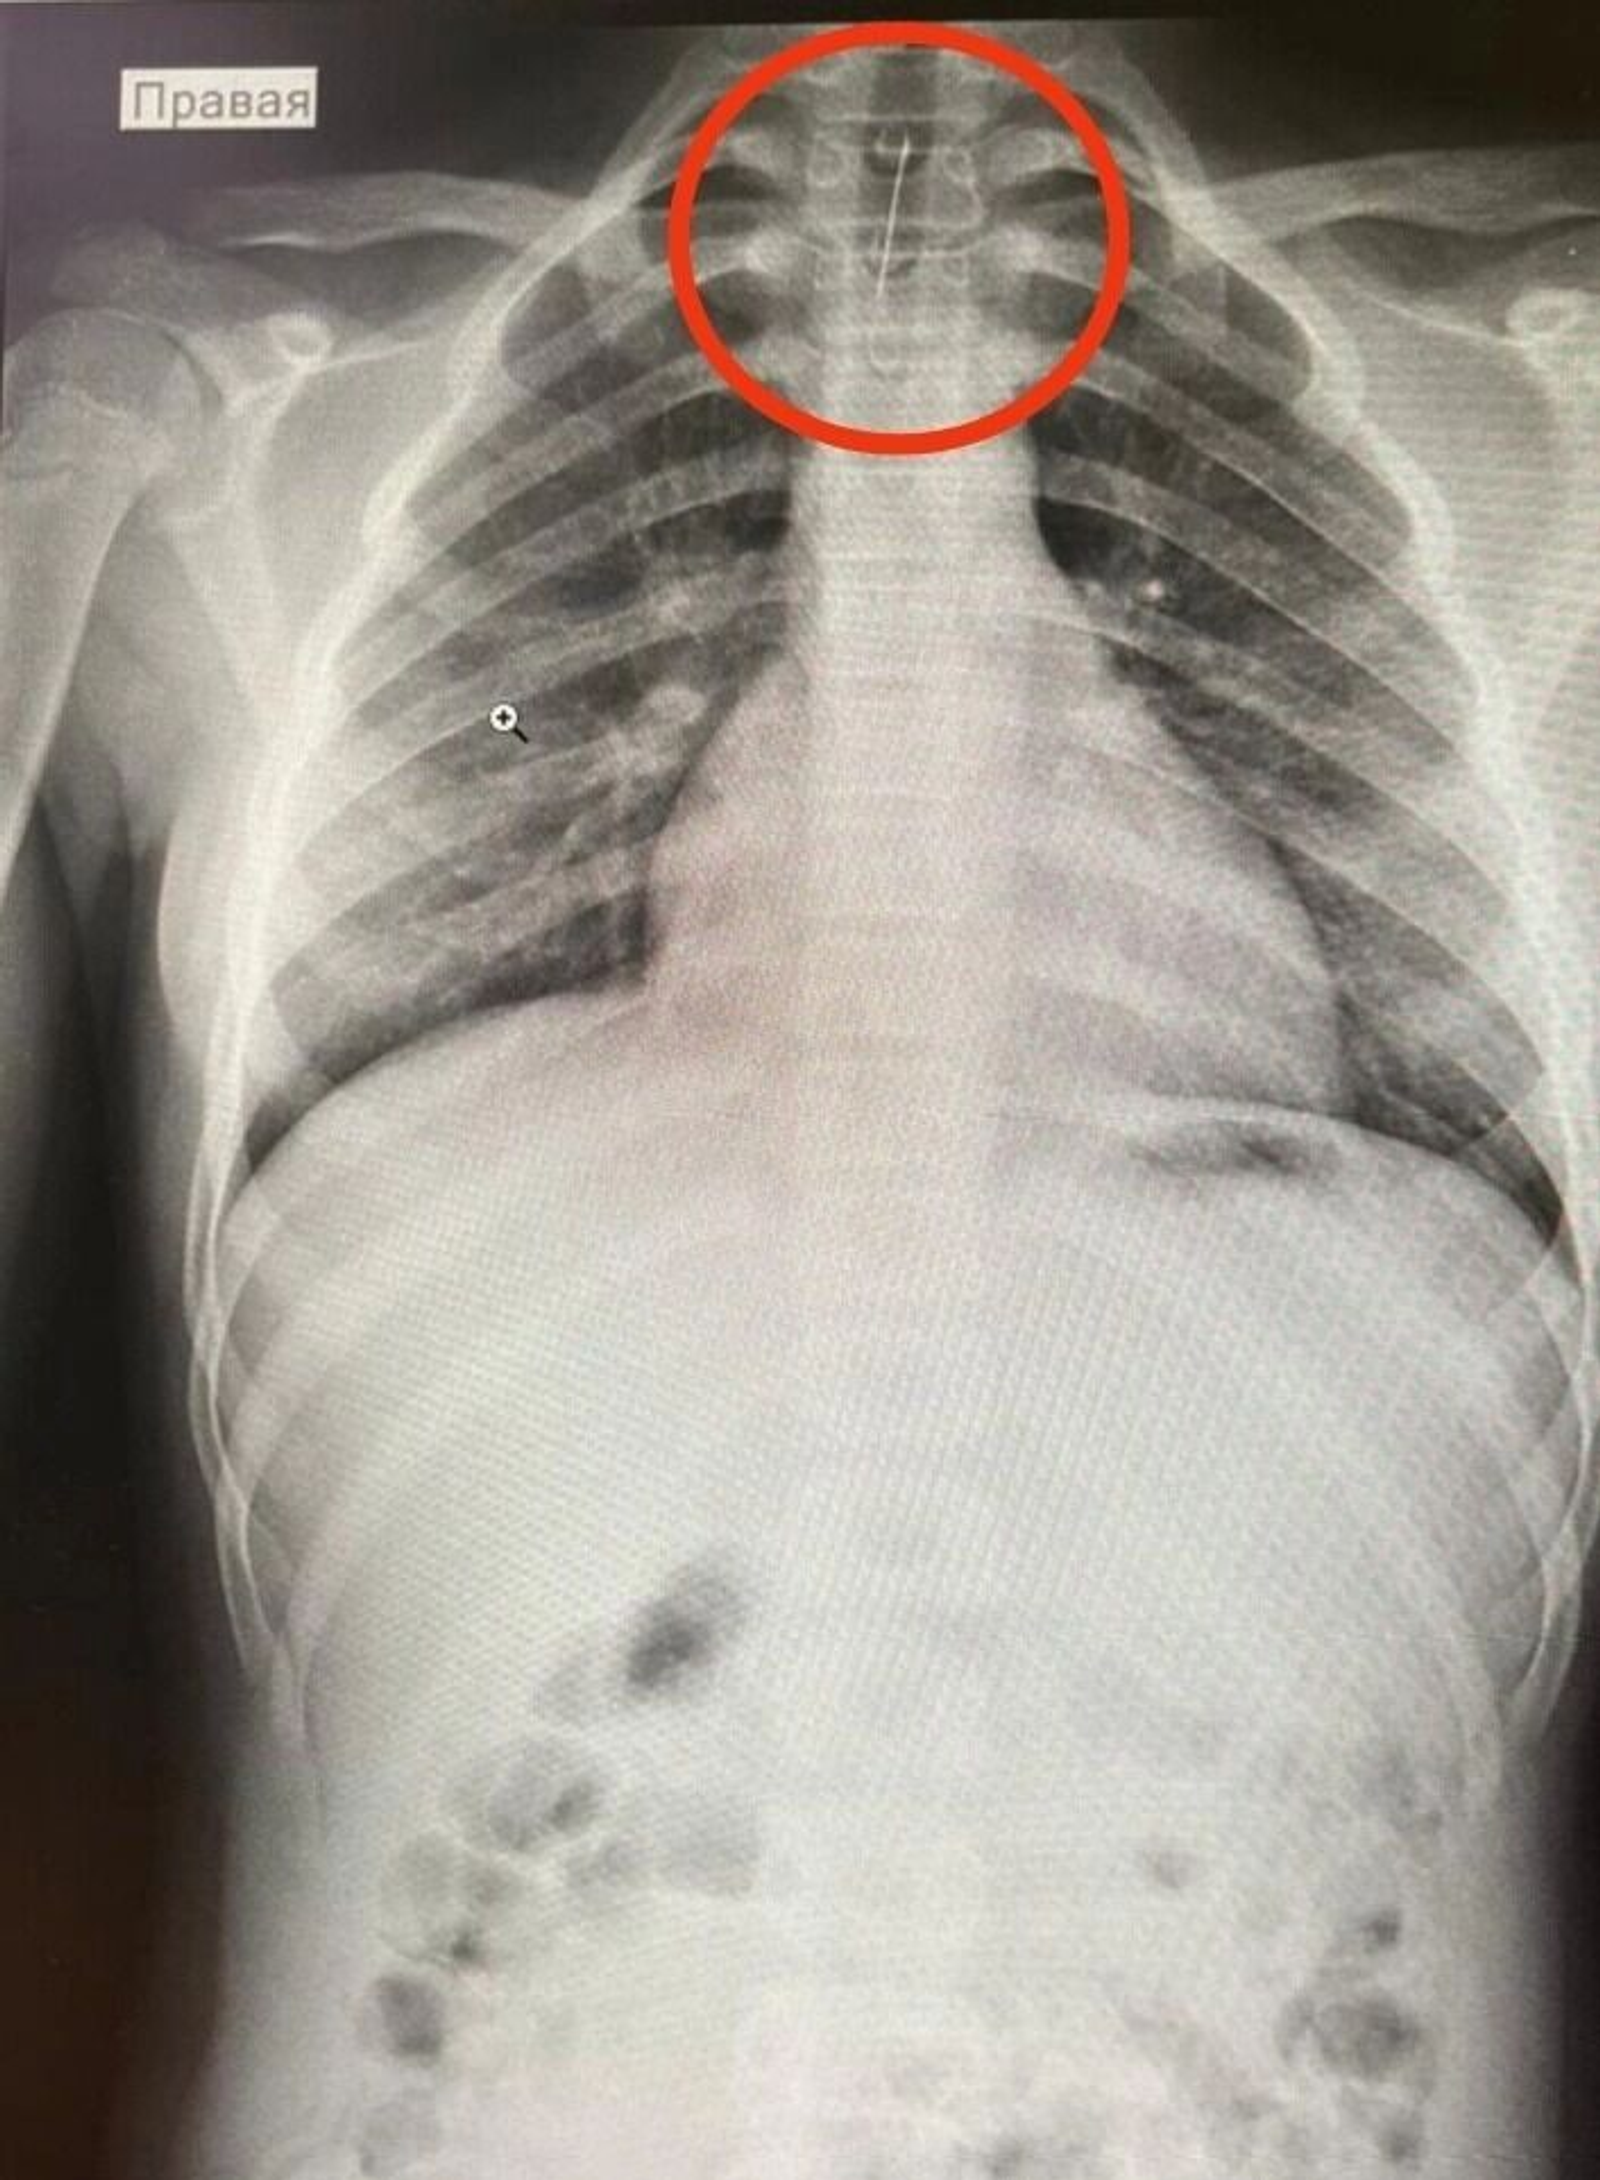

Хирург провёл осмотр пациентки, сделал ФГДС и рентген, на котором было обнаружено инородное тело в трахее. После консультации с педиатром-хирургом Республиканской детской клинической больницы по линии санавиации девочку отправили в Уфу.

В столице Башкирии были проведены повторные обследования. Благодаря оперативным действиям врачей иглу удалось аккуратно извлечь с помощью бронхоскопии, что помогло избежать серьёзных осложнений.